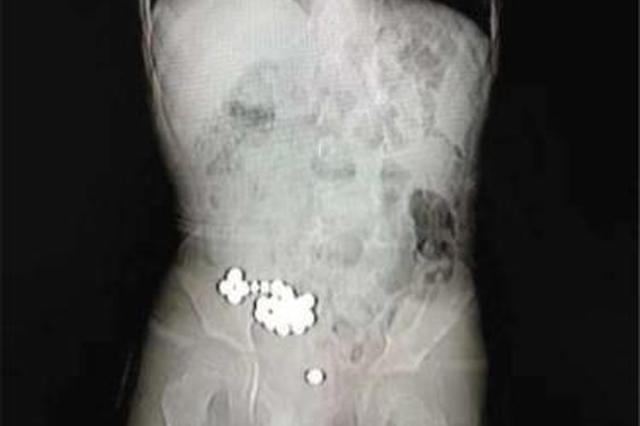

图为男童体内的磁力珠。医院供图

但3天过去了,磁力珠仍未排出,明明还不时地哭喊肚子痛,这下可把明明父母急坏了,赶紧带孩子去医院拍片。在X光片下,一排磁力珠清晰可见,细数竟有20颗之多,每颗珠子的直径约为0.5厘米。随后,父母连夜把明明送到了宁波市妇儿医院急诊科,经过一系列检查,明明被送入手术室。